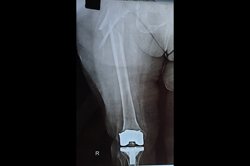

Total Knee Replacement - TKR